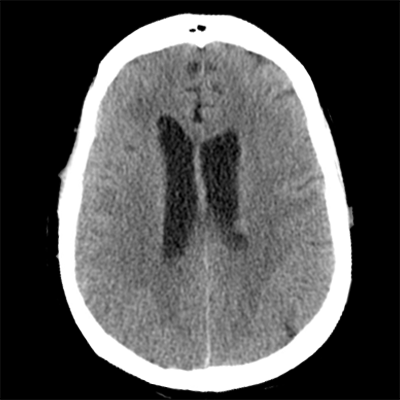

You arrive at the patient's room. You quickly examine her. Her left pupil is truly dilated and unreactive. Her right pupil is also dilated and unreactive, and also deviates to the right. She is unable to follow commands but is moving her extremities spontaneously. The right side of her body seems to be moving slightly less than her left. You escort the patient with RRT and your neurology colleague to radiology, where a non-contrast head CT and CTA head/neck are obtained.

The non-contrast head CT looks generally similar to her prior scan. There's no new hemorrhage anywhere. There's no mass effect causing midbrain compression. The vessel imaging also looks unrevealing-- a slightly hypoplastic right A1 segment, but no clear LVO in either the anterior or posterior circulation. There's no vasoconstriction.